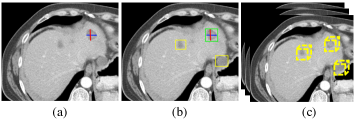

Universal lesion detectors (ULDs) [1, 2], which aim to discover various types of lesions in multiple organs on radiological images, fit the daily clinical need of general radiologists and thus have significant clinical values. Due to the success of deep learning in computer vision, most ULDs are deep convolutional neural networks (DCNNs), which require a large-scale annotated image dataset to train. Unlike labeling natural images, annotating medical images is costly and requires extensive domain knowledge [3]. The various appearances of lesions on medical images make it even more challenging to annotate all lesions thoroughly. For instance, the large-scale CT image dataset with RECIST annotations [4] for various kinds of lesions, namely DeepLesion, is reported to have 50% lesions unlabeled (see Fig. 1).